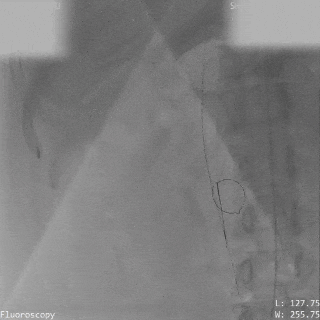

锁定后评估

牵拉试验

牵拉试验确认封堵器稳定

释放后评估

封堵器形态良好,基本无残余分流